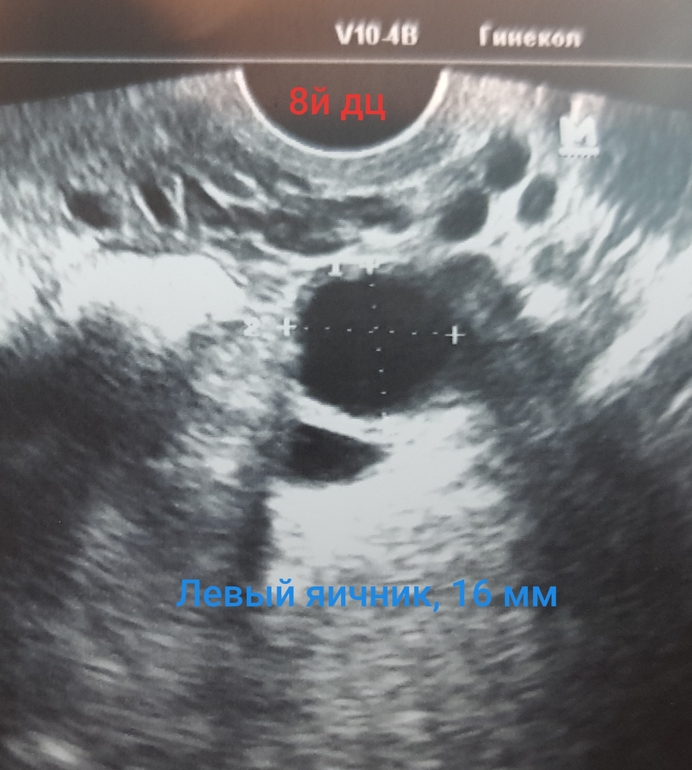

На стимуляции, была на узи (фото ниже) на 8й, 11й и 16й дц.

На 8й было в ЛЯ 16мм и в ПЯ 16, 15, 14 (3 дф)